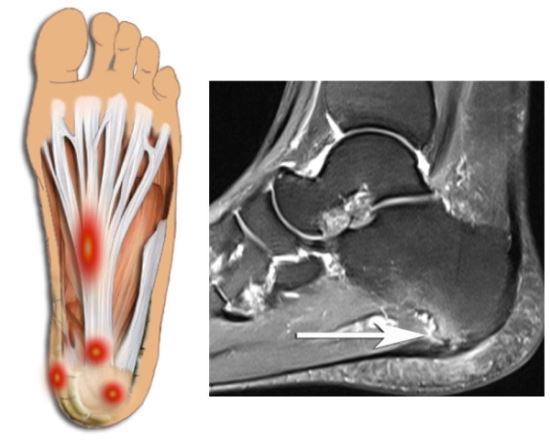

발 뒤꿈치에서부터 발바닥 앞쪽까지의 발바닥 근육을 감싸고 있는 두꺼운 근막이 "족저근막"이라고 합니다. 족저근막이 발바닥의 아치를 유지하고, 걸을 때 스프링처럼 완충 작용을 하여 발을 보호해 주는 기능을 하는데, 이 족저 근막에 반복적인 미세 손상을 입어 염증이 발생한 것을 "족저근막염"이라고 합니다. 대게 40~50대의 여성에게 많이 발생합니다.

대부분 발바닥 중앙 부분부터 통증이 시작되어 발바닥이 걷거나 서 있는 동안에 더 심하게 통증이 느껴지집니다. 아침에 일어나자마자 첫 발을 디딜 때 발바닥에 통증이 심합니다. 움직임에 따라 호전될 수도 있지만 다시 통증이 나타날 수 있습니다. 발바닥 근막염이 생기게 되면 발바닥 부위에 염증과 부종이 생기게 될 수 있으며, 발바닥 힘줄 부근에 압력이 가해지면 민감하게 반응하게 됩니다. 그리고 오래 걷거나 뛰거나 활동할 때 통증이 더 심해질 수 있습니다.